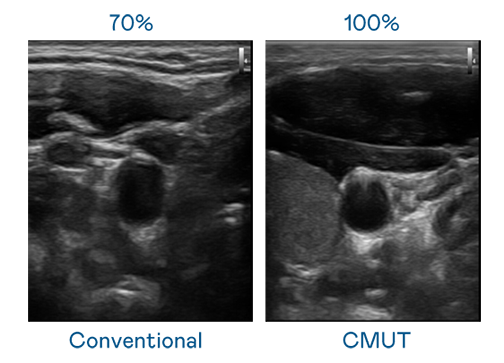

CMUT 技术是一种用电容式微机电元件来产生超音波讯号的技术。与传统 PZT 压电式技术相比,CMUT 频宽增加 30%,更宽频的超音波讯号让影像解析度大幅提升,是实现高影像品质医疗超音波扫描、促进精准医疗发展的关键技术。

大频宽带来超清晰影像

超音波影像的解析度高低,首先取决于探头能发出的讯号频宽。征途国际 CMUT 可提供高清晰的超音波讯号,提供高频宽、高灵敏度、影像纹理细节更高的超音波影像,协助医护人员缩短影像判读时间及利用精准的医疗影像进行诊断。